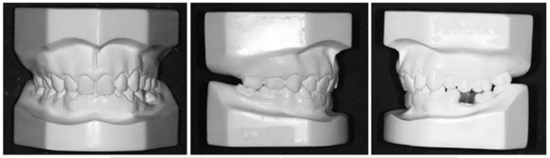

3.體格檢查:直面型,露齦笑,深覆合、合平面傾斜(Figure 1)。上中線偏右3mm,下中線偏左2mm。磨牙II類關(guān)系,左側(cè)尖牙II類關(guān)系,右側(cè)尖牙I類關(guān)系,左下第二磨牙低位咬合,右上前磨牙缺失。覆蓋率為100%,覆蓋度為4mm。咬合平面重度傾斜,左側(cè)向下移位(Figure 2、3)。

上下頜牙齒均粘貼0.022x0.028英寸的MBT托槽(3M / Abzil)并且使用0.014英寸的鎳鈦絲到0.020英寸的不銹鋼弓絲排齊、整平。

之后,在左上前磨牙之間植入種植釘,作為支抗,將右上部牙列向后移動至I類關(guān)系(Figure 6a-c)。原本想采用微種植釘體來矯正傾斜的咬合面,然而,微種植釘動度大,并且不能承受較大的負荷。取而代之的是,在左側(cè)上頜骨植入微鈦板作為支抗,用兩個懸臂(其用0.018x0.025英寸鈦-鉬絲制成)連接至鈦板上的兩個管并且系緊在弓絲上,以此壓低左側(cè)上頜后牙。此外,使用橫腭桿來避免左側(cè)后牙的頰傾(Figure 6d,e)。